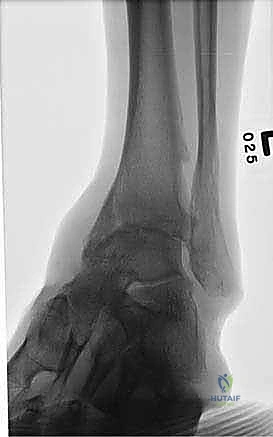

- الأشعة السينية أثناء الوقوف (Weight-bearing X-rays): هي الفحص الذهبي والأهم. يجب أن تؤخذ الأشعة والمريض واقف لتحمل الوزن. تظهر الأشعة تضيق المسافة المفصلية (دليل على فقدان الغضروف)، وجود نتوءات عظمية، تصلب العظم، وأي انحراف في محور المفصل.

- التصوير المقطعي المحوسب (CT Scan): يطلبه الدكتور هطيف لتقييم جودة العظام (Bone stock)، تحديد حجم الأكياس العظمية، ورسم خريطة ثلاثية الأبعاد للتشوهات المعقدة قبل الجراحة.